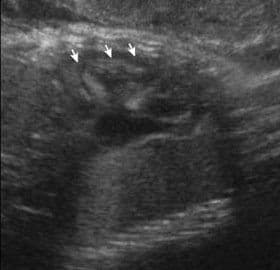

This bright spot is usually first detected during the second-trimester anatomy ultrasound, and many parents are naturally concerned about what it means. The first thing you need to know is that this finding is usually not an indication of abnormal cardiac anatomy and usually is a normal finding.

There is no complete agreement from the experts about this finding and there is conflicting evidence for an increased risk of Down syndrome. The published risks of Down syndrome among fetuses with echogenic cardiac foci have varied from no increased risk up to a four-fold increase in the age-related risk. Several studies suggested a risk of about 1%. That means that 99/100 babies with this finding will not have Down syndrome.